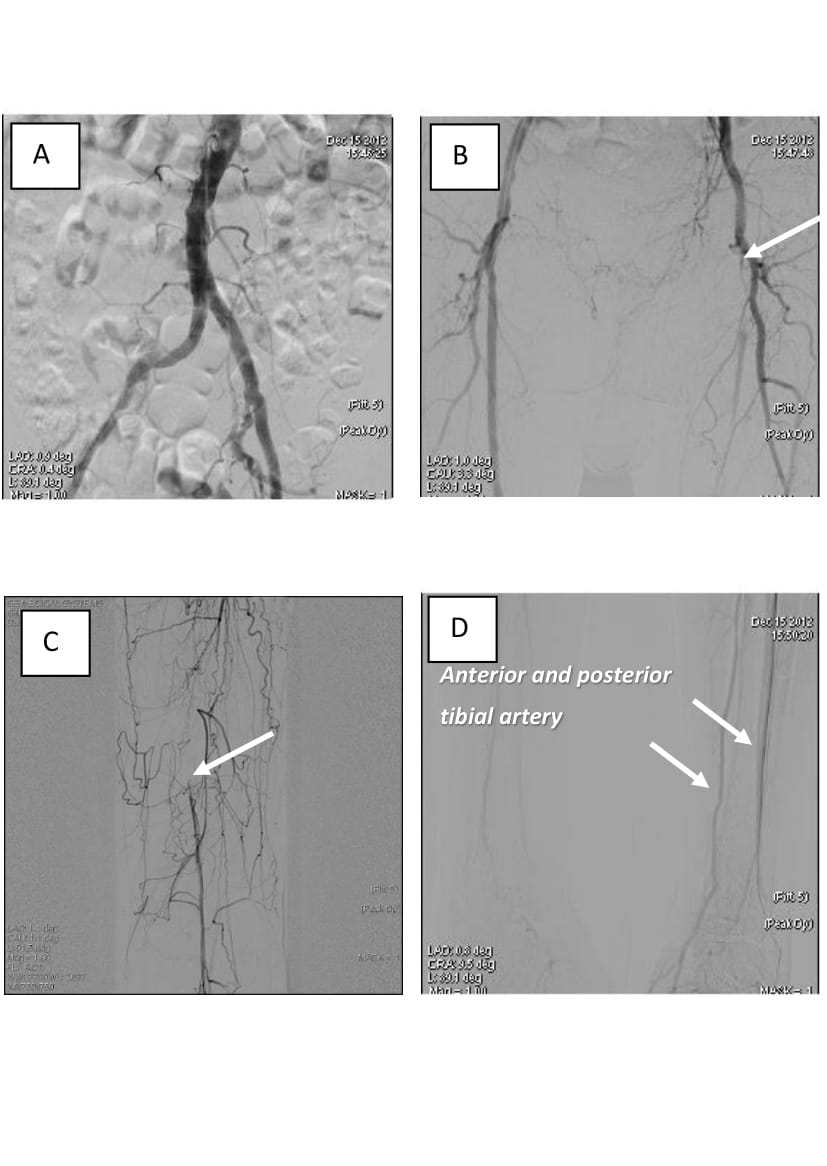

In aortoarteriography, pronounced atherosclerotic alterations in the arteries of the infrainguinal segment were revealed. Mild stenosis of the common femoral artery up to 30%, occlusion of the superficial femoral artery from the orifice to the popliteal artery, occlusion of the popliteal artery and critical stenosis of II segment of the popliteal artery were visualized. Significant (60%) stenosis of the posterior tibial artery was identified. Stenosis of the arteries of the shin. The arterial arch of the foot preserved (Figure 5).

Fig. 5. Angiograms of patient M., 70 years old: А – aorto-iliac segment, without hemodynamically significant stenosis; B – occlusion of the superficial femoral artery (shown by arrow); C – hemodynamically significant stenosis of the popliteal artery (shown by arrow); D – shin arteries (shown by arrow), distal peripheral resistance evaluated as 3 points